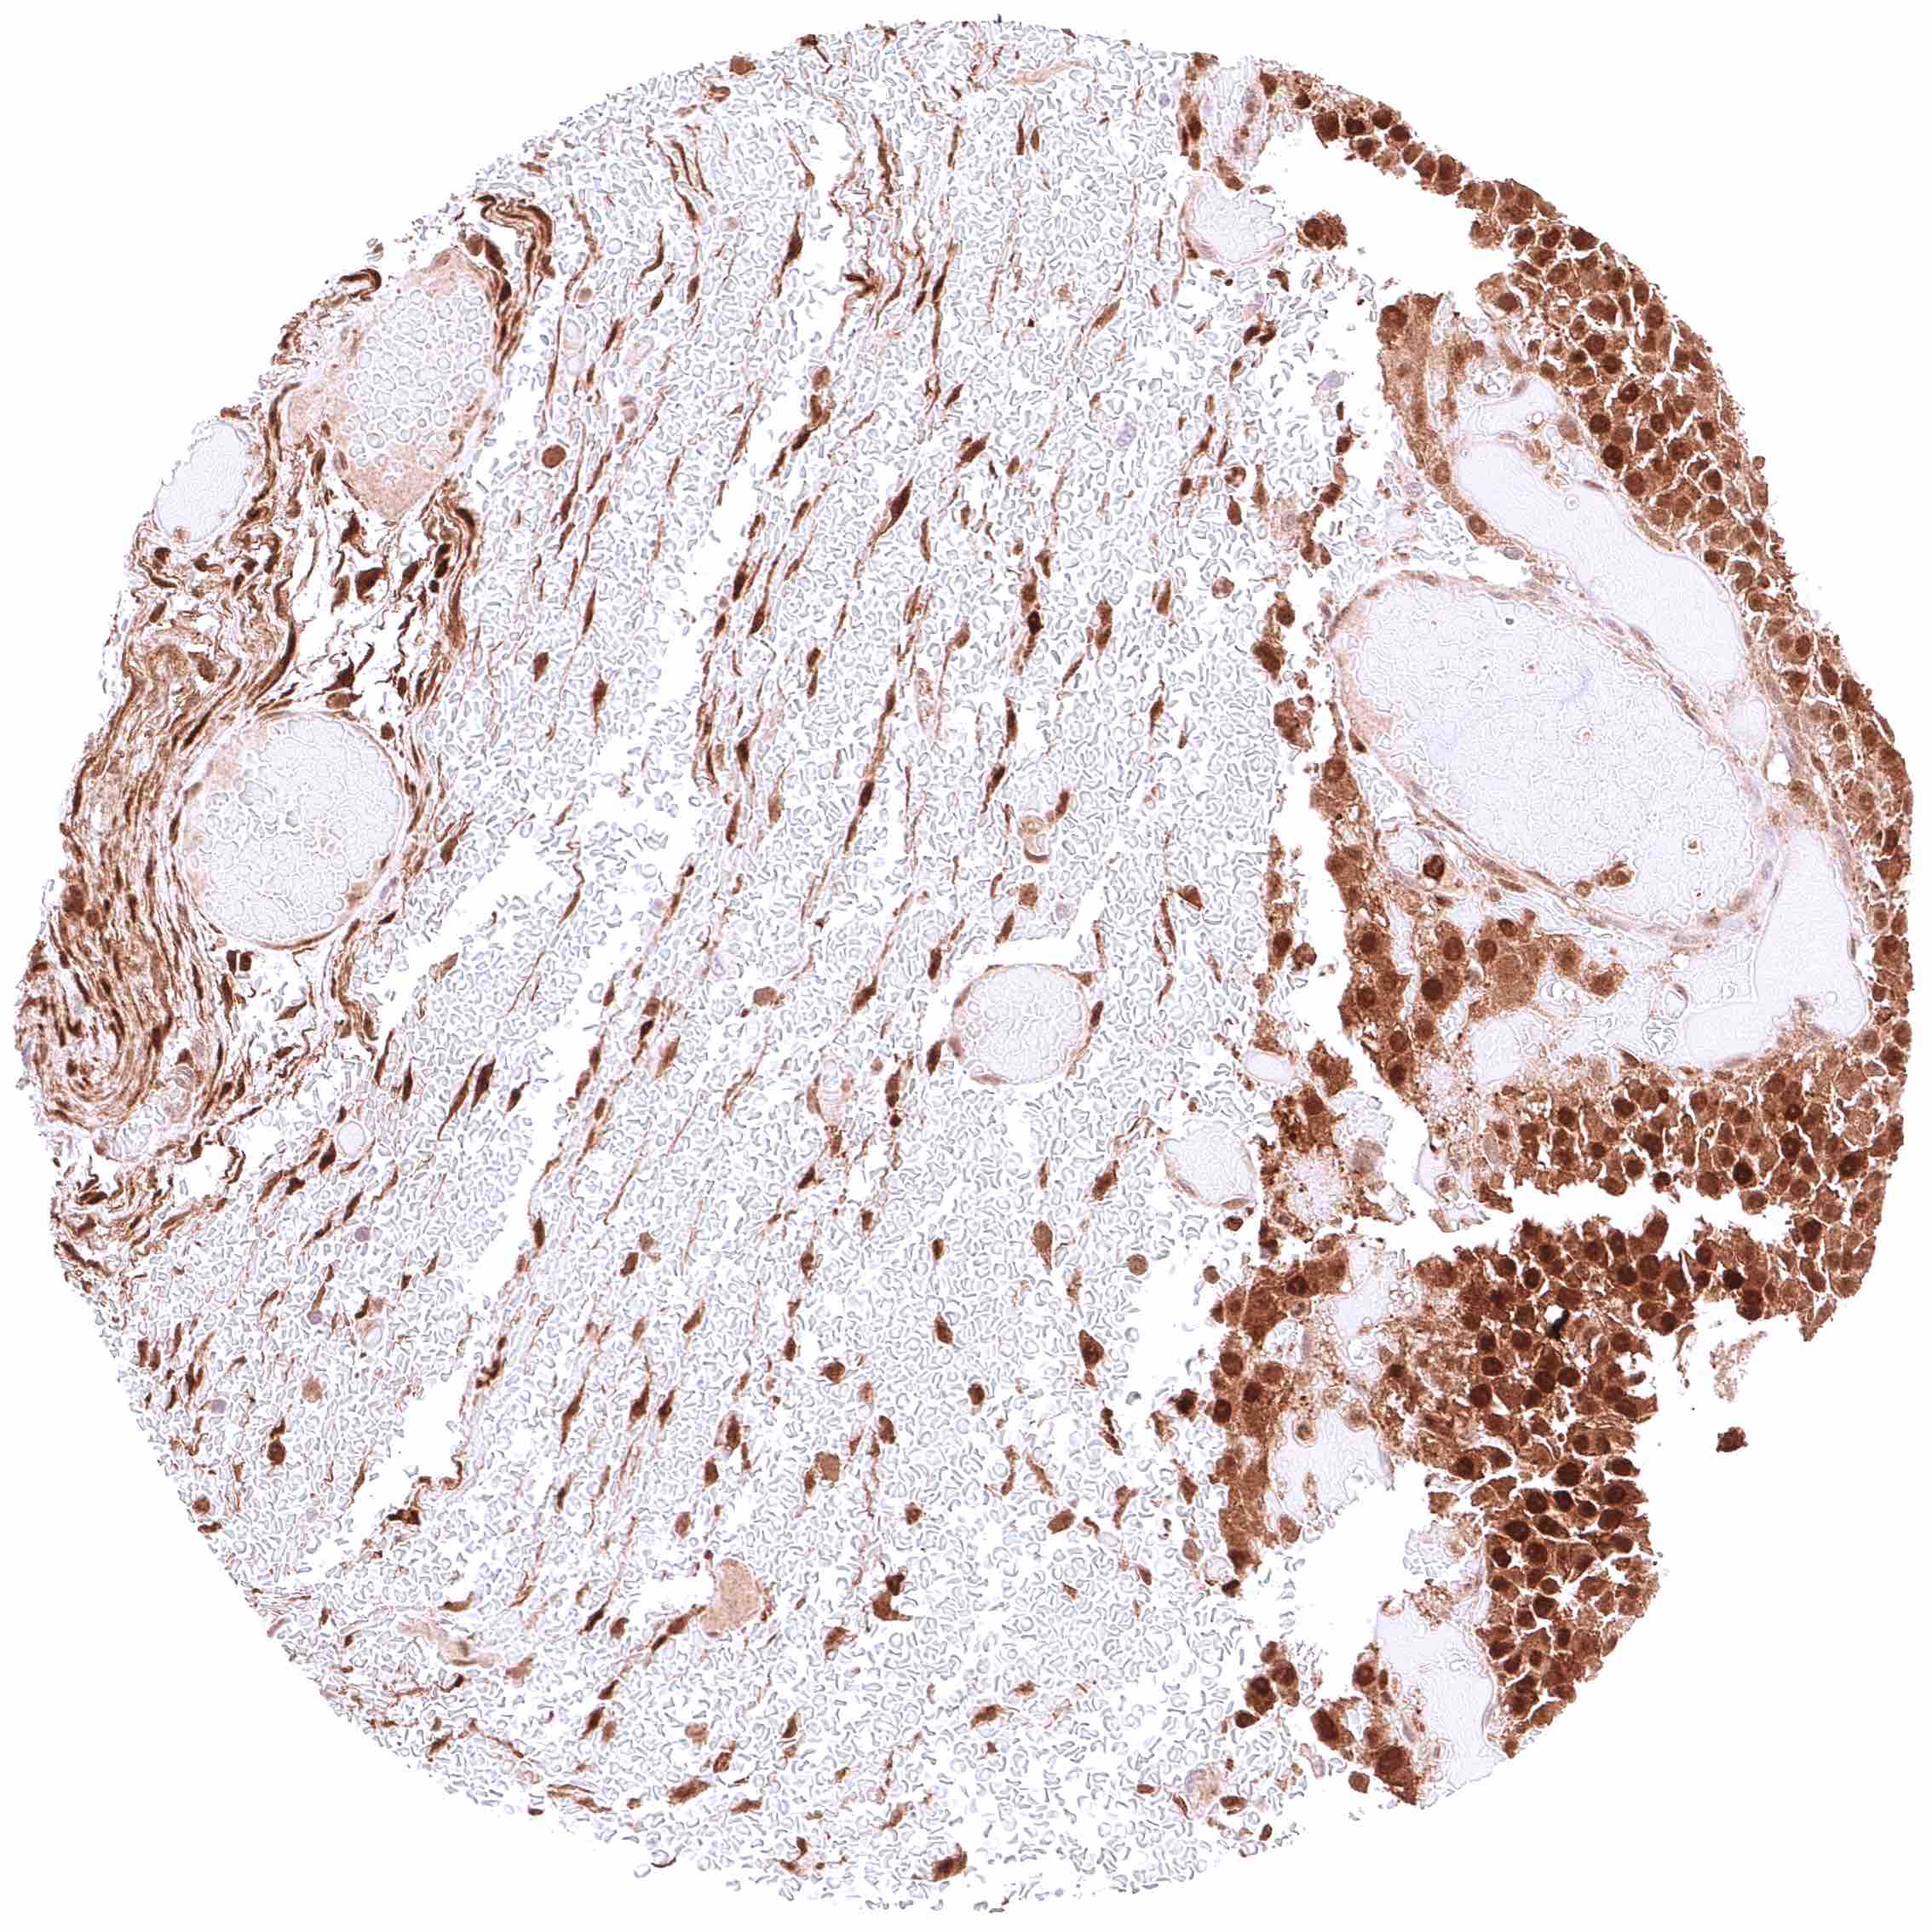

Skin – Strong nuclear and cytoplasmic GSTP1 positivity of all squamous epithelial cells.

Skin, ekkrine glands – Strong GSTP1 positivity of eccrine glands.

Skin, hairfollicle and sebaceous glands – Strong GSTP1 positivity of hair follicles and peripheral germinative cells of sebaceous glands while sebaceous cells remain GSTP1 negative.